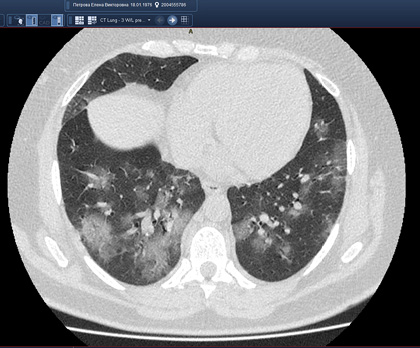

Routine clinical laboratory assays were performed in the hospital’s clinical laboratories. Clinical and laboratory information was extracted from the patients’ medical records. C reactive protein (CRP) in plasma was measured by immunoturbidimetry (Beckman Coulter, Krefeld, Germany). Interleukin-6 (IL-6) levels in plasma were measured by electrochemiluminescence (Siemens Medical Solutions Diagnostics, Siemens Healthcare, Erlangen, Germany). CT scans were read by experienced radiologists who scored results by severity using the criteria shown in Figure 1.

Figure 1. Clinical assessment of pneumonia severity based on computed tomography (CT) scores.

Scoring method: Mild (CT-1)—no more than three ground-glass opacities of <3 cm maximum diameter. Moderate (CT-2)—more than three ground-glass opacities; less than 50% involvement by visual assessment. Medium-heavy (CT-3)—ground-glass opacities and pulmonary consolidation; 50-70% involvement by visual assessment. Severe (CT-4)—diffuse ground-glass opacities with or without consolidation; more than 75% involvement by visual assessment.